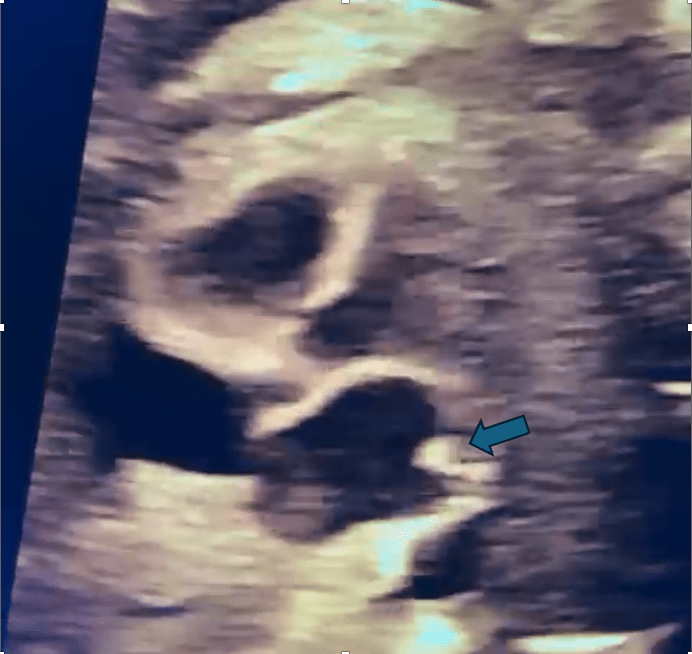

Presence of a Confluence Behind the LA (Twig Sign)

- Identifying a venous confluence posterior to the LA is a vital clue. The absence of a normal Coumadin ridge can complement this.